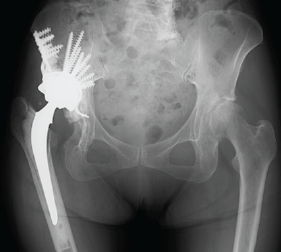

Treatment of Hip Osteoarthritis with Severe Acetabular Bone Defects by Total Hip Arthroplasty Using the Restoration GAP II Reinforcement Ring: A Case Report

Akira Yuasa , Hiroki Kobayashi , Keisuke Horiuchi

………………………………p.179-182